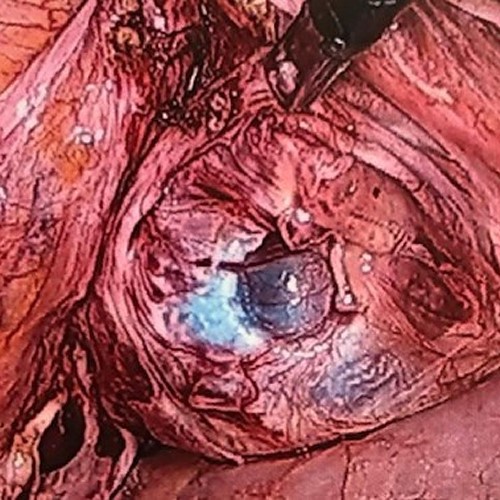

At laparoscopy, dehiscence of the vault was identified, and the peritoneal covering was opened (Fig. 2). Healed tissue at the vaginal edge was excised and both vaginal edges sutured with interrupted Polyglycolic acid No1suture, in two layers after mobilizing the bladder adequately. A nonabsorbable mesh (Polypropylene 6 × 11 cm) was placed onto the vault, extending 2 cm onto both anterior and posterior vaginal walls. Mesh was anchored to both the anterior and posterior vaginal walls with interrupted 2-0 proline (Figs 3 and 4). We used another 1.5 cm × 11cm mesh to anchor the vault to the sacral promontory. Mesh was extended via a retroperitoneal tunnel and anchored to sacral promontory with nonabsorbable helical fastener (Covidien ProTack Auto suture, 5 mm). Vaginal vault and the full extent of the mesh were completely covered with the peritoneum using Polyglycolic acid no 2.0 continuous suture. Intravenous Co-amoxyclave and metronidazole was given for 48 h. Six weeks following surgery the vaginal vault was well healed. She was followed up for 6 months and recovered completely without any long-term complications.